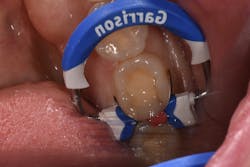

The failing composite restoration was removed along with the recurrent decay. A new restoration was placed using VisCalor bulk (figure 2). The flowability of theClinical case no. 2

The lower left second molar was prepared for a class II composite restoration (figure 3). A sectional matrix band was placed and wedged. The preparation was etched, and adhesive was placed and cured. The VisCalor bulk was heated in the heating gun and then dispensed into the base of the box while in its flowable state. Note the complete adaptation of the material to the walls ofEditor's note: This article appeared in the November 2021 print edition of Dental Economics.